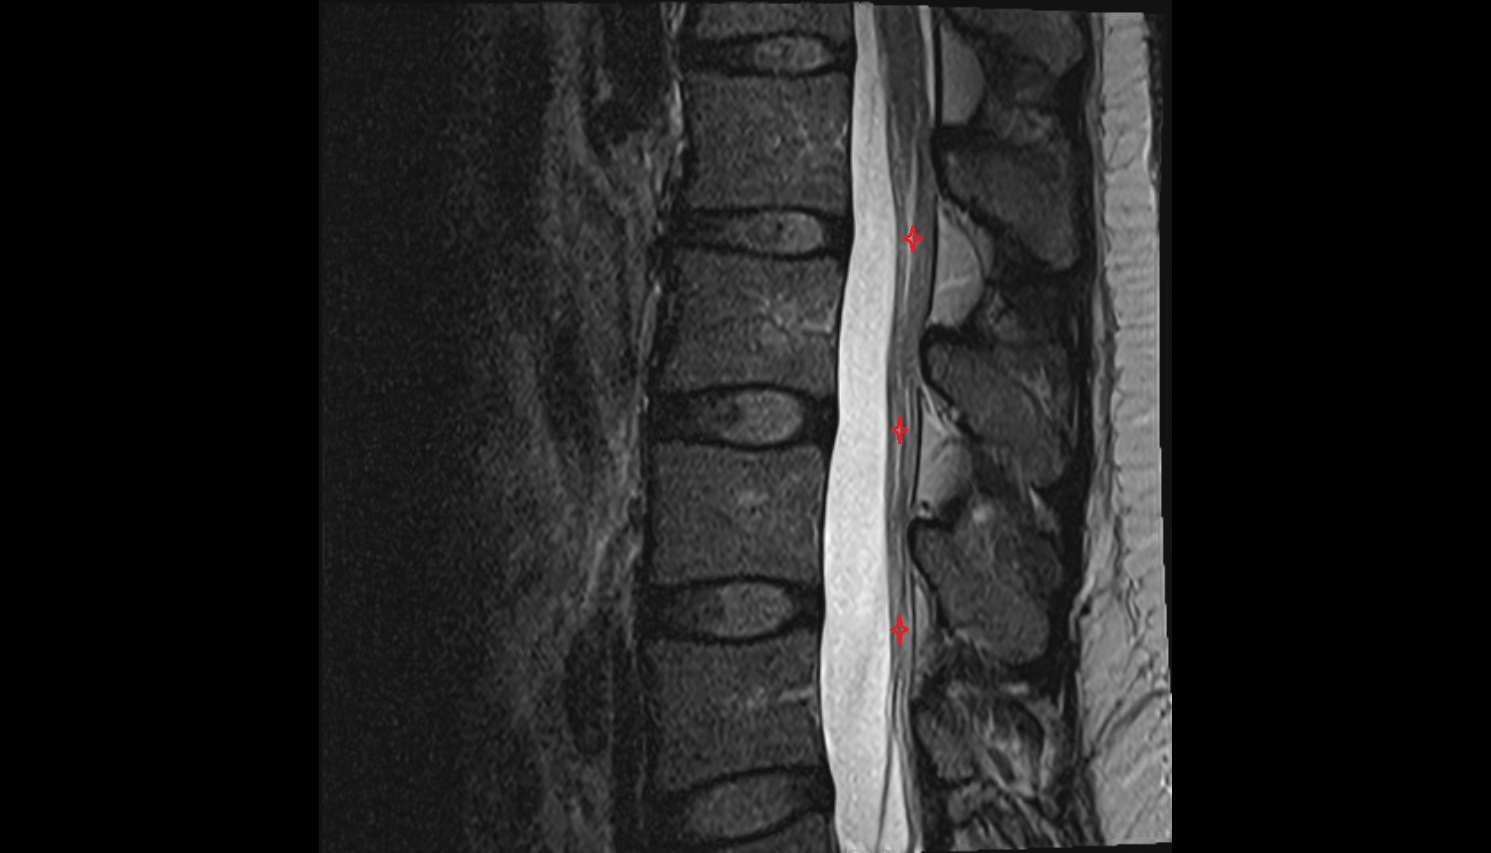

- L5–S1 Intervertebral disc

- L4–L5 Intervertebral Disc

- L3–L4 Intervertebral Disc

- L2–L3 Intervertebral Disc

- L1–L2 Intervertebral Disc

- Cauda equina

- Conus medullaris